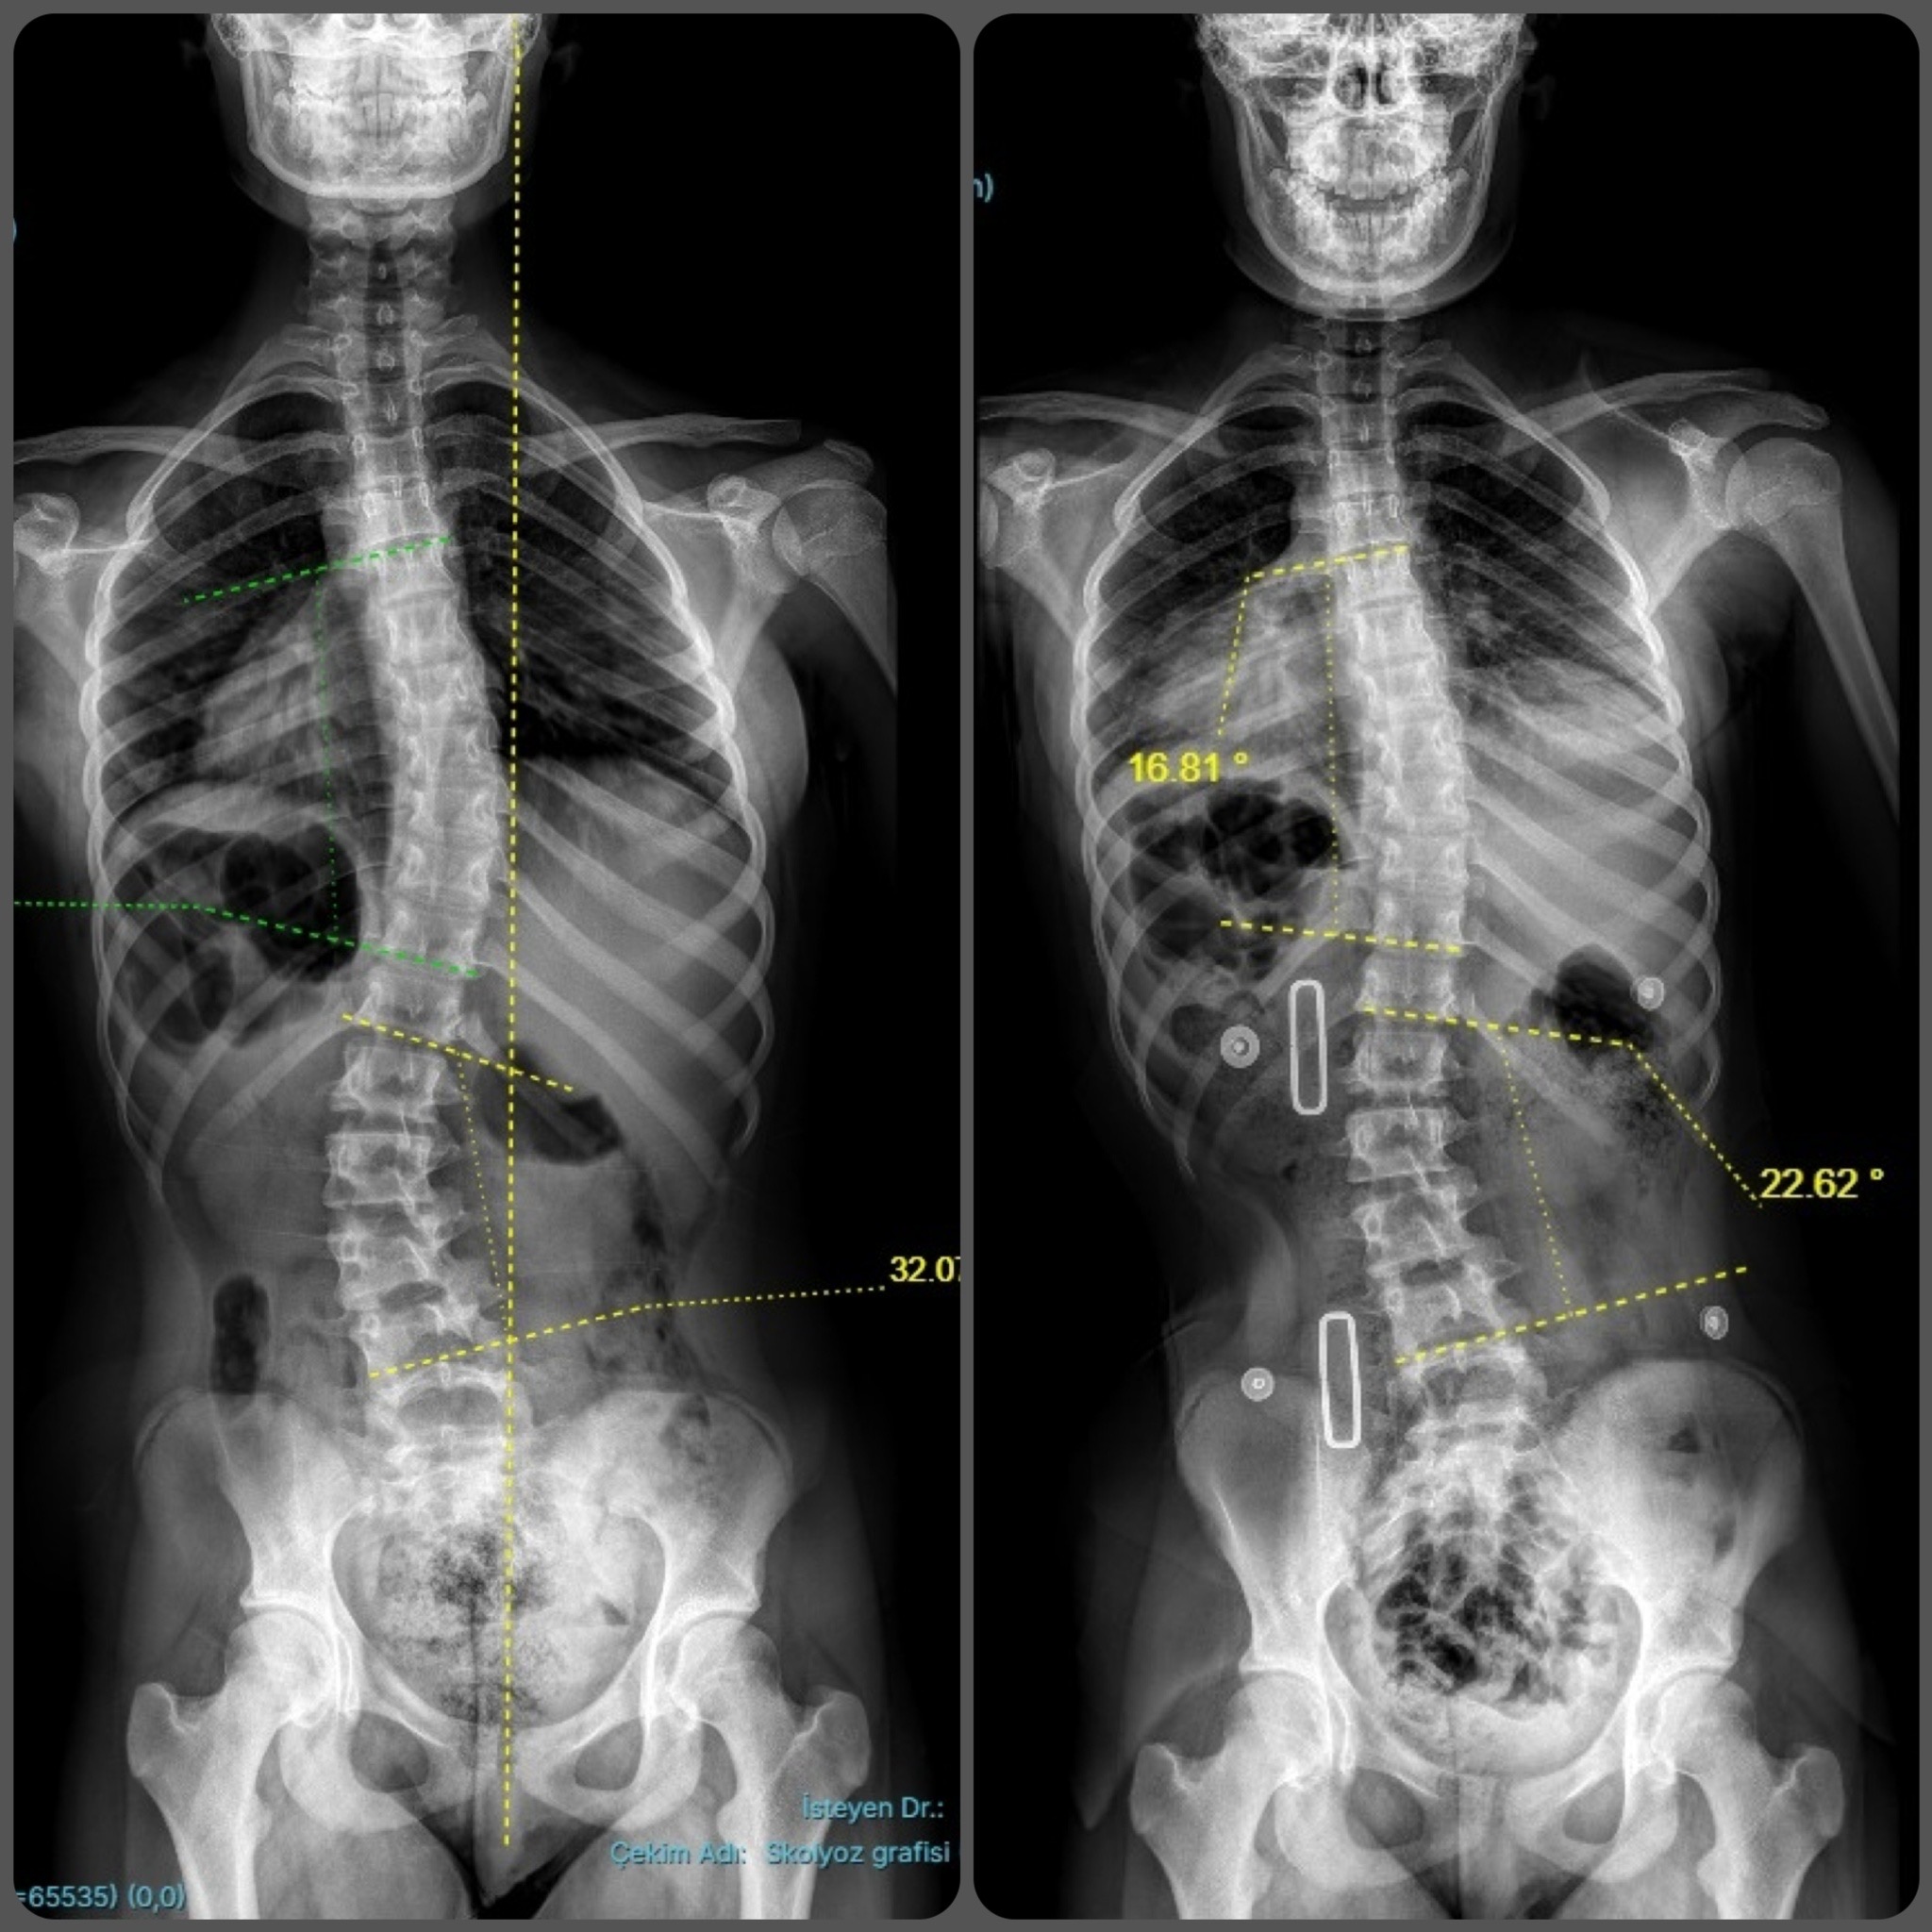

CAD/CAM (Bilgisayar Destekli Tasarım) sistemlerimizle, röntgen üzerindeki eğrilik derecesine (Cobb açısı) tam zıt kuvvet uygulayan, asimetrik Gensingen/Cheneau tipi korseler tasarlıyoruz.

Uyguladığımız 3D korseler ile elde ettiğimiz düzeltme sonuçlarından bazı örnekler.